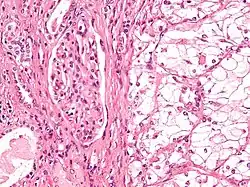

Papillary transitional cell carcinoma, renal pelvis, with urinary obstruction and pyelonephritis

The most common type of kidney malignancy is renal cell carcinoma,[35] which is thought to originate from cells in the proximal convoluted tubule of the nephron.[15][36] Another type of kidney cancer although less common, is transitional cell cancer (TCC) or urothelial carcinoma of the renal pelvis.[37] The renal pelvis is the part of the kidney that collects urine and drains it into a tube called the ureter.[37] The cells that line the renal pelvis are called transitional cells, and are also sometimes called urothelial cells. The transitional/urothelial cells in the renal pelvis are the same type of cells that line the ureter and bladder. For this reason TCC of the renal pelvis is distinct from RCC and is thought to behave more like bladder cancer.[37] Other rare types of kidney cancers that can arise from the urothelial cells of the renal pelvis are squamous cell carcinoma and adenocarcinoma.[15]